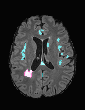

In recent years, data-driven machine learning (ML) methods have revolutionized the computer vision community by providing novel efficient solutions to many unsolved (medical) image analysis problems. However, due to the increasing privacy concerns and data fragmentation on many different sites, existing medical data are not fully utilized, thus limiting the potential of ML. Federated learning (FL) enables multiple parties to collaboratively train a ML model without exchanging local data. However, data heterogeneity (non-IID) among the distributed clients is yet a challenge. To this end, we propose a novel federated method, denoted Federated Disentanglement (FedDis), to disentangle the parameter space into shape and appearance, and only share the shape parameter with the clients. FedDis is based on the assumption that the anatomical structure in brain MRI images is similar across multiple institutions, and sharing the shape knowledge would be beneficial in anomaly detection. In this paper, we leverage healthy brain scans of 623 subjects from multiple sites with real data (OASIS, ADNI) in a privacy-preserving fashion to learn a model of normal anatomy, that allows to segment abnormal structures. We demonstrate a superior performance of FedDis on real pathological databases containing 109 subjects; two publicly available MS Lesions (MSLUB, MSISBI), and an in-house database with MS and Glioblastoma (MSI and GBI). FedDis achieved an average dice performance of 0.38, outperforming the state-of-the-art (SOTA) auto-encoder by 42% and the SOTA federated method by 11%. Further, we illustrate that FedDis learns a shape embedding that is orthogonal to the appearance and consistent under different intensity augmentations.